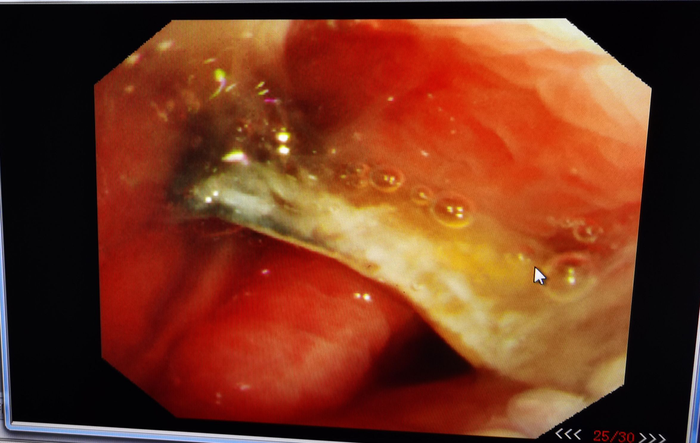

患者女,55岁,因“咯血半个月”入院。

入院后查血常规、凝血功能、D-二聚体、心电图均正常。胸部CT如下:

图1

胸部CT仅见左肺上叶少许炎性改变,这种很常见的影像改变,非常容易让人大意以为就是普通的细菌感染而造成漏诊或误诊。

其实够用心或者有足够经验就会意识到,这点病灶不至于引起这样的咯血。为了明确咯血原因,我们给她做了支气管镜检查,虽然病灶在支气管的远端,支气管镜下未发现异常,但我们常规给予支气管肺泡灌洗液(BALF)送检。

支气管肺泡灌洗液培养结果回报有“出人意料”的重要大发现——见到黄曲霉。

于是我们换4.0mm直径的细支气管镜进入该支气管亚段再次检查,发现左上叶上舌段亚段内白色坏死物,为了进一步确诊,我们给予钳检。

图2

钳检病理回报见真菌孢子及菌丝样物,故该患者实际上不是细菌感染,而是曲霉菌感染所致,治疗上予注射用伏立康唑(0.2g,每日2次)治疗。50天后复查支气管镜,原病灶处明显好转,气管镜下予伏立康唑局部注射治疗。

图3

这个病例告诉我们对于不明原因的咯血不要忽略了做支气管镜检查,同时提醒我们就算支气管镜下未发现病灶,也很有必要在相应的可疑部位做灌洗留取标本检查协诊。

此外,笔者还想提醒大家的是,支气管肺泡灌洗液半乳甘露聚糖(GM)测定对肺曲霉病的诊断具有较高的敏感度和特异度,千万别满足于只做常规的涂片和培养。